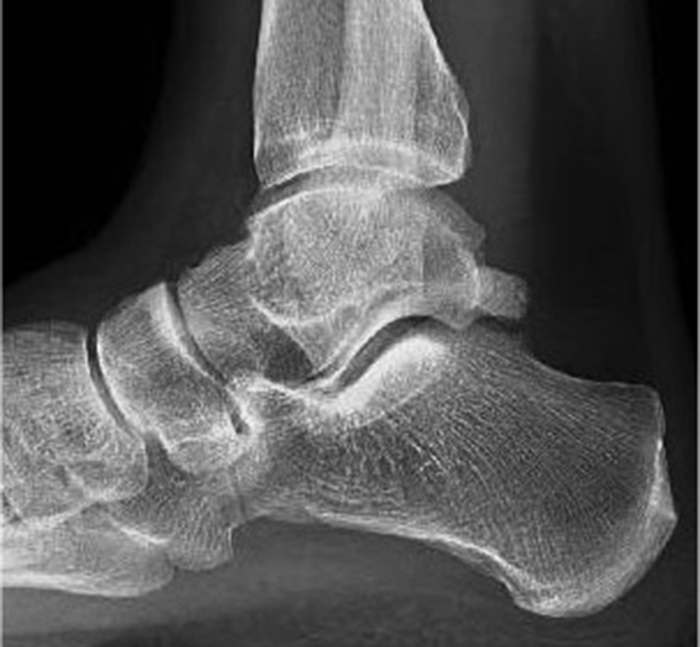

Pinzamiento de tobillo o impingement. Qué es, síntomas y tratamiento

En la imagen mostramos una radiografía lateral en carga de un paciente con limitación a la flexión dorsal del tobillo. El paciente padece el síndrome…